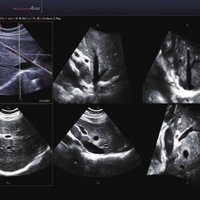

Das Samsung Accuvix A30 ist ein hochwertiges Ultraschallsystem, das mit seiner 3D-Technologie herausragende Ergebnisse ermöglicht. Das Sonographiegerät besitzt 5 Sondenanschlüsse und ist mit 20 unterschiedlichen Schallköpfen kompatibel. Mit dem A30 können Schallköpfe vom Typ Konvex, Mikrokonvex, 3D-Konvex, CW, Phased Array, Linear und Endokavitär verwendet werden. Bei zwei der Sonden handelt es sich um S-VUE Ultraschallsonden, die durch ihre höhere Bandbreite noch feinere Scans erzeugen.

Das Ultraschallsystem hebt sich besonders durch seine 3D-Technologie wie die Face Auto Detection für detaillierte Ultraschallbilder von Föten oder das Volume Shade Imaging, das sich auf die lebensnahe Darstellung von Schattierungen und Hauttönen fokussiert, ab. Mit weiteren wertvollen Technologien wie dem ElastoScan™ werden Tumore schneller erfasst und durch die HD Volumen Bildgebung sowie das DMR+™ eine erstklassige Bildqualität erzielt.